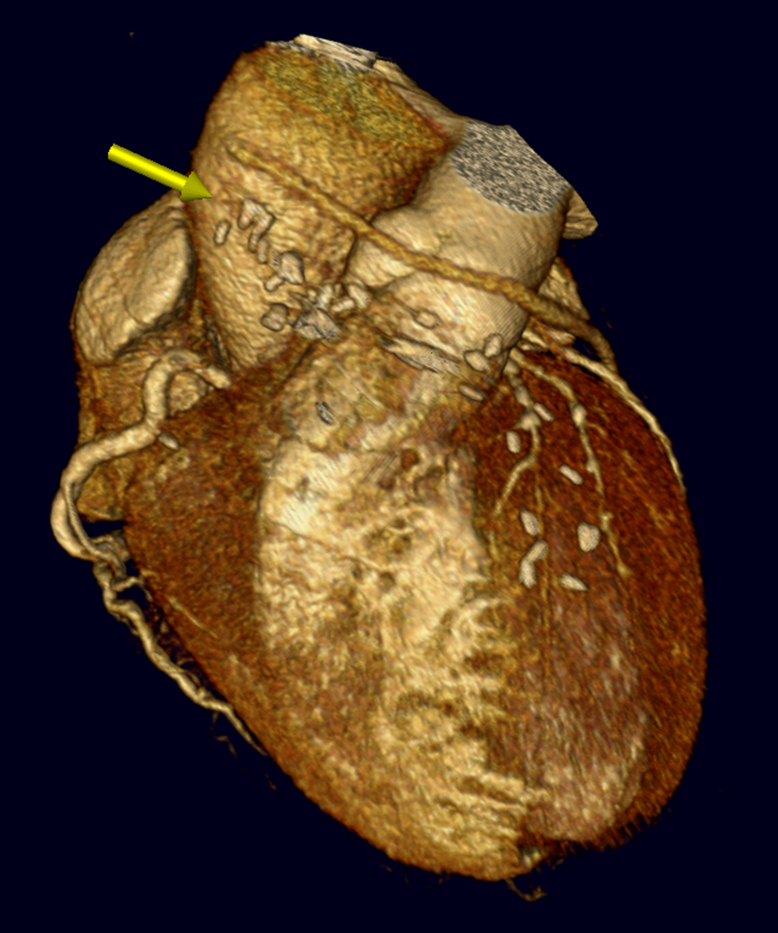

The non-invasive imaging modality of multi-detector computed tomography has dramatically evolved the last ten years and that is due to hardware and software developments. The newer generation of scanners allows increased spatial and temporal resolution that improves the clinical reliability giving further insights into the evaluation of coronary artery disease. Heart morphology imaging followed by studies of myocardial function and assessment of cardiac valves can be performed from the information derived from the data of the coronary artery examination. Also, the venous anatomy of the heart, coronary artery bypass grafts, stents, and cardiac tumors can be imaged and evaluated when necessary. For the beneficial use of this method, entrance criteria for different patient groups need to be set in order to allow improved outcome of multi-detector CT.